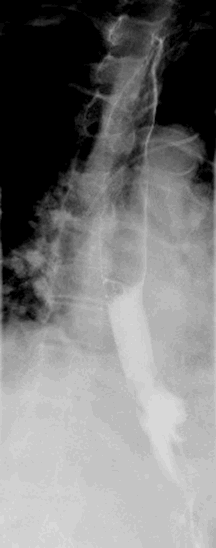

Her stents were removed, and EVAC therapy was initiated. The technique for EVAC foam placement is described below in the discussion. The foam was placed through the perforation site into the cavity in the left mediastinum. EVAC placement was performed under general anesthesia. She was discharged to an in-house, long-term acute care facility and treatment continued. She required ten foam exchanges every three days to one week for 41 days with a progressive decrease in fluid extravasation into the chest and eventual discontinuation of both chest tubes and mediastinal drain. Upper GI at the completion of therapy showed no evidence of a leak (Figure 2). On long-term follow up, her jejunostomy tube had been removed, and she is tolerating a regular diet without dysphagia or reflux.

Figure 2. Upper GI with no evidence of leak at completion of therapy